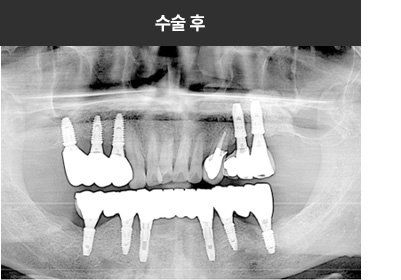

BMP를 이용한 수술 사례      I

치료 기간 : 2023.03.22 ~ 2023.09.15

* 상기 사례의 경우, 해당 의료기관에서 진료를 한 환자분의 동의를 얻어 사용되었습니다. * 치료 전후의 사진은 동일 인물과 동일한 조건에서 촬영 되었음을 알려드립니다.

* 모든 수술 및 시술은 개인에 따라 부작용고지 : 임플란트치료는 치료 후 감염,

염증, 연조직합병증, 출혈, 감각이상 등의 부작용이 있을 수 있습니다.

의료진과 충분히 상의 후 신중하게 결정하시기를 바라겠습니다.